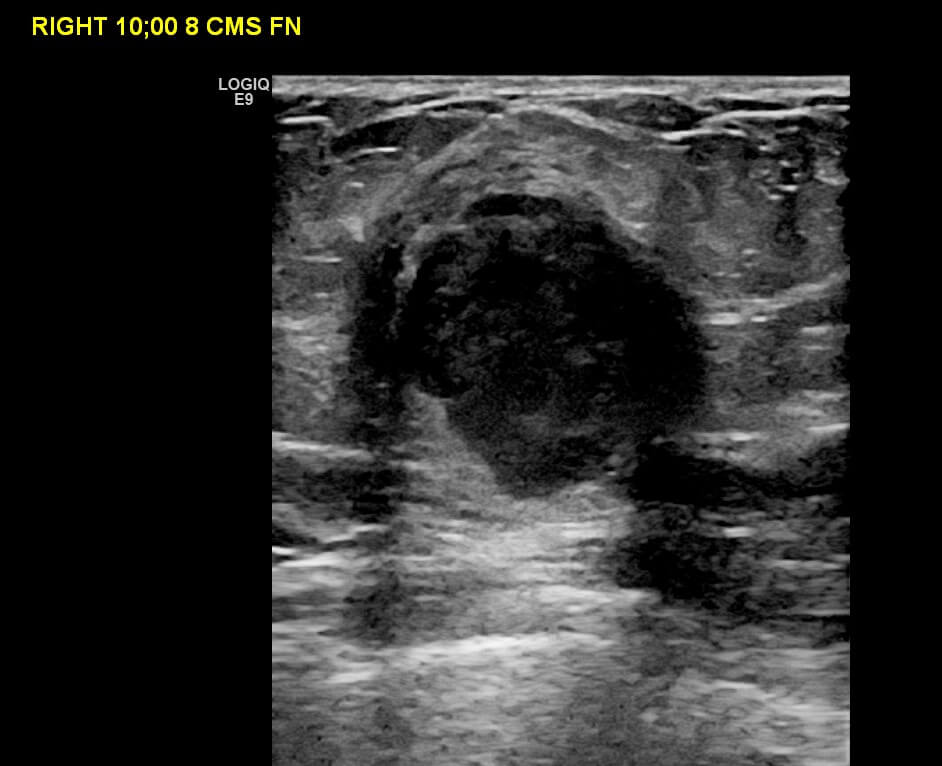

Mammogram revealed the presence of an irregular high density mass in the posterior third of the upper outer quadrant of the right breast with indistinct margins on two-dimensional mammogram. No internal calcification seen. No overlying skin thickening or retraction noted. DBT (Digital breast tomosynthesis) revealed the mass having spiculated margins and irregular shape. Corroborative ultrasound showed an irregular, heteroechoic solid mass at 10-11 O’clock position with anti-parallel orientation, microlobulated margins, posterior enhancement and internal necrotic/ cystic areas within. Mild internal vascularity was seen on color Doppler. No dilated ducts or intraductal extension was seen. No suspicious lymph nodes were present Further recommendation: Ultrasound guided core-needle biopsy with immunohistochemical analysis Management received: Right side lumpectomy with MRM Final histopathology: Metaplastic carcinoma (carcinosarcoma) with no nodal metastasis

Overall BI-RADS category 4B Differential diagnosis: Atypical or malignant phylloides, tumors like mucinous carcinoma, triple negative breast cancer, metaplastic carcinoma